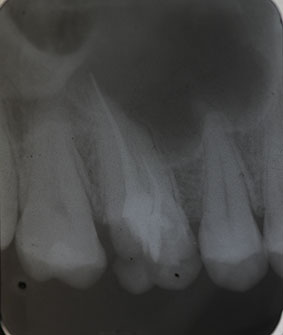

Nach Darstellung aller Wurzelkanaleingänge wird in einem zweiten Schritt das frakturierte Wurzelkanalinstrument dargestellt (Abb. 3 u. 4). Hierfür verwenden wir den Aufsatz 3E des Tigon+. Durch die schmale und lange Form des Instruments erreichen wir einen tiefen und schmalen Zugang.

Abb. 3 u. 4: Zustand nach Revision des Wurzelkanals und Darstellung des frakturierten Instruments.